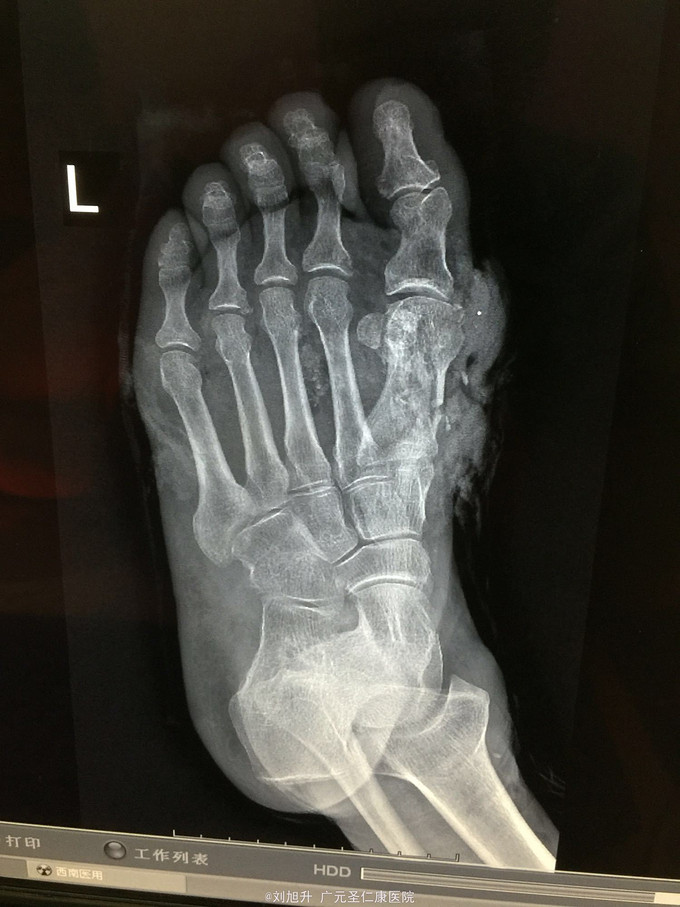

左足背砸伤

患者,男,61岁,因左足背重物砸伤5小时入院